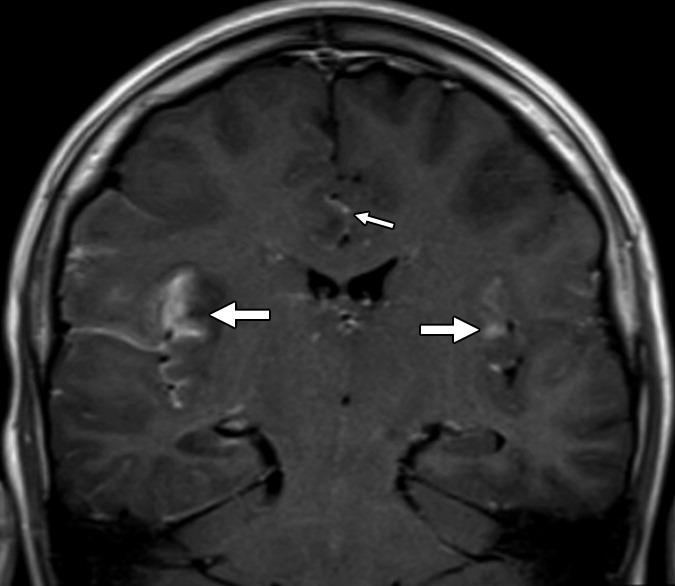

Рисунок 1 | Асимметричные области патологически повышенного МР сигнала в медиальных отделах обеих височных долей, больше выраженные в корковом веществе

Рисунок 2 | В последовательности DWI у того же пациента определяются области повышения сигнала в обоих лобно-височных областях. ИДК подтвердила ограничение диффузии

Т1-взвешенное корональное изображение после введения контраста демонстрирует асимметричное двустороннее гириформное и лептоменингальное контрастное усиление больше в области коры островка (большие стрелки) и поясной извилины (меньшая стрелка)